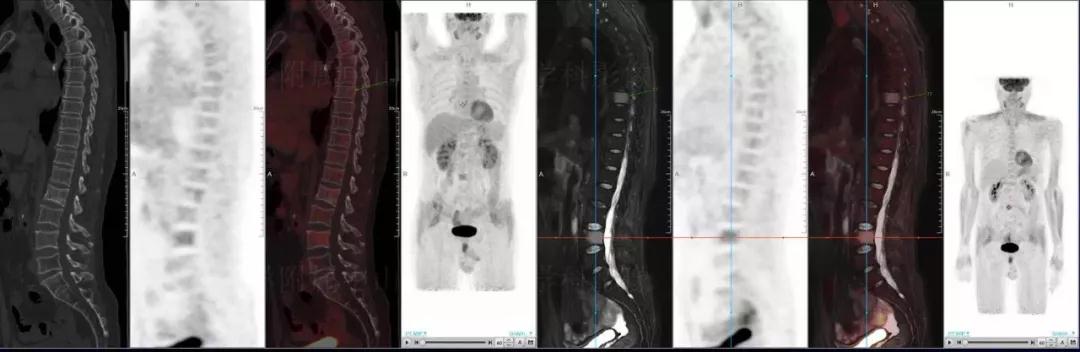

多發(fā)性骨髓瘤

中山醫(yī)院核醫(yī)學(xué)科基于聯(lián)影“時空一體”超清TOF PET/MR的融合顯像優(yōu)勢,進(jìn)行了大量的臨床掃描,發(fā)現(xiàn)多例由MGUS向多發(fā)性骨髓瘤轉(zhuǎn)變,并從中總結(jié)出了一定的共同征象,未來可能實現(xiàn)多發(fā)性骨髓瘤的早期篩查。此外,PET/MR在多發(fā)性骨髓瘤的療效評估方面,也存在顯著優(yōu)勢。

(男性,53歲。確診多發(fā)性骨髓瘤10月。經(jīng)過7周期VCD方案化療后,現(xiàn)行療效評價。)